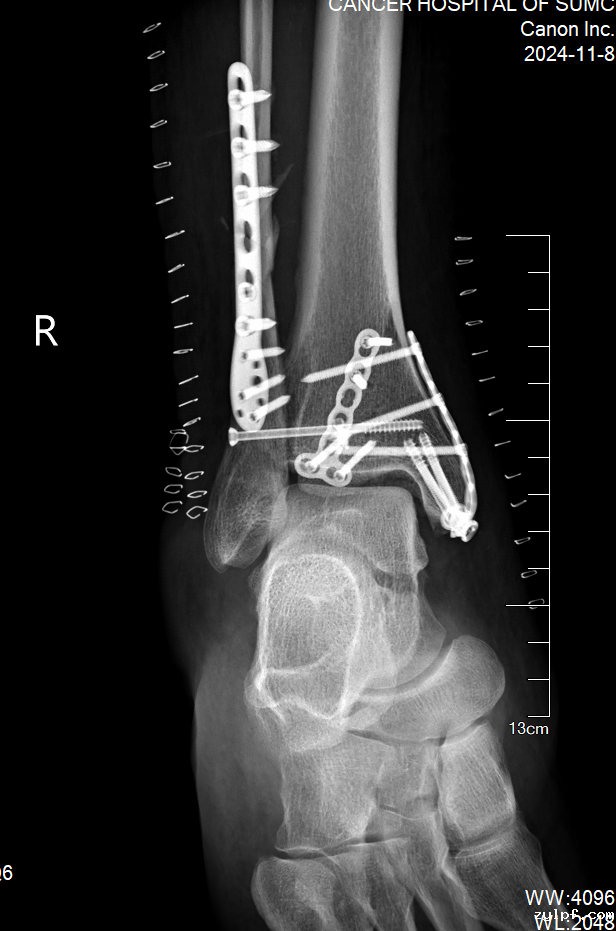

在这10天里,医院骨科医护团队对患者进行了精心的照料,并时刻同患者保持积极的沟通。随着右踝关节肿胀的逐渐消退,手术的时机也日益成熟。最终,凭借精湛的技术,患者右胫腓骨远端骨折达到了解剖复位。

患者术后复查骨折端解剖复位

术后,患者按计划开始了早期的康复治疗,整个康复计划包括物理治疗、功能锻炼和心理辅导,在医护人员的悉心照料下,患者的右踝关节活动能力日渐恢复。出院两周后,患者返回医院进行复查。检查结果显示,患者的右踝活动功能良好,骨折部位固定良好。患者对医护人员的精湛医术和悉心照料表示了深深的感激。